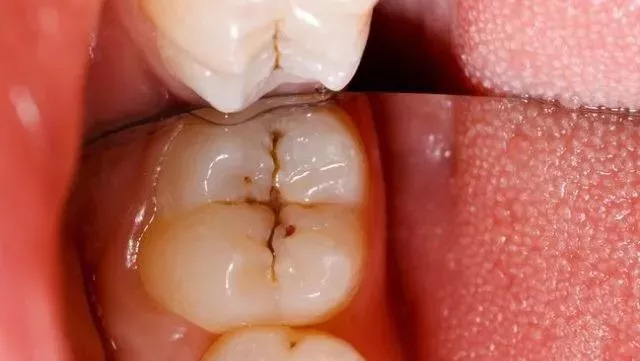

我们常说的后牙,学名第一磨牙和第二磨牙,是磨碎食物的主要牙齿,也是最坚硬,最大的牙齿。首先我们需要了解后牙窝沟点隙的结构,即发育沟。后牙的表面即咬合面,一般会有四个隆起角,由牙胚发育而成。四个隆起部位之间形成沟壑点隙。这些沟壑的形态不同,而这些沟壑最容易附着堆积污垢细菌,形成窝沟龋,窝沟龋形态千变万化,每个人的样子都不同,但大致都会有明显的黑线模样。

窝沟的形态与龋坏的进展速度是密切相关的。窝沟是不易清洁的,在窝沟发生龋坏时,损害是从窝沟侧面开始(釉柱和密度决定),最后扩展到窝沟底部,当窝沟龋进一步发展,达到牙本质层时,龋坏速度就会加快。直到腐蚀到牙髓,疼痛就开始了。

牙齿出现黑线预示着什么?一旦牙齿沟出现黑线,很不幸,说明你已经蛀牙了!不要单纯的以为那只是色素累积,早期蛀牙是没有龋洞的,平时饭后没有注意漱口,容易造成食物残渣堆积,给口腔细菌提供了营养,在唾液环境下,导致牙齿表面(牙釉质)被破坏。

早期的后牙有蛀牙是没有明显的龋洞,大多在咬合面有黑色的勾线,很多患者都以为那是色素沉着,洗牙时总是要求尽力把那洗去,殊不知那其实已经是龋坏。

1、蛀牙基本形成,沟壑内附着细菌,牙齿表面黑线形成。